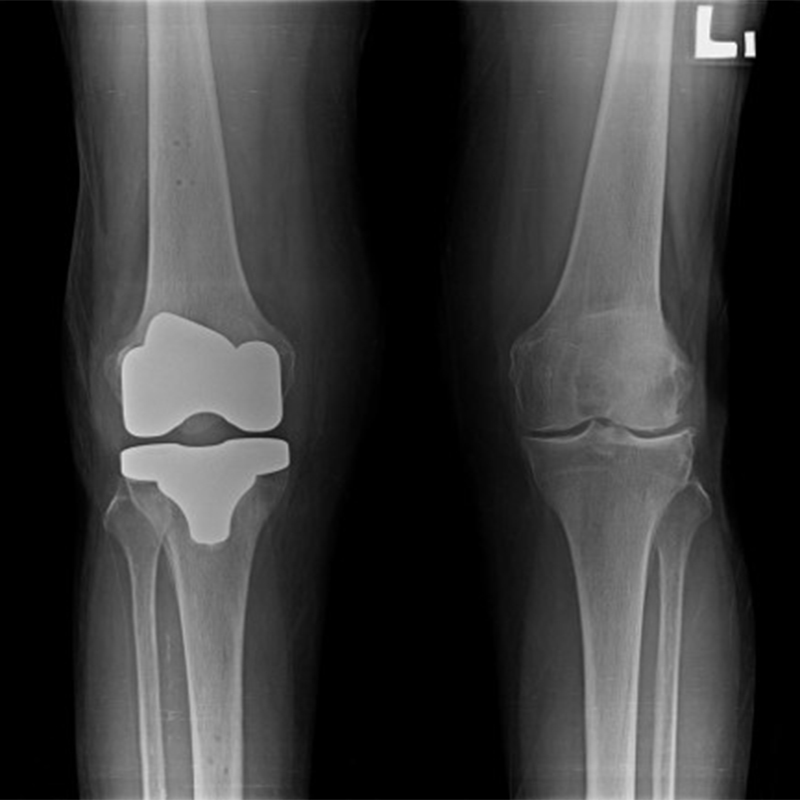

機器手臂手術 首頁 案例分享 膝關節手術 機器手臂手術 蔡女士 78歲 術前 術後 陳女士 70歲 術前 術後 術前 術後 ANGEVINE女士 73歲 術前 術後 U.S.A Mark 73歲 術前 術後 藍女士 78歲 術前 術後